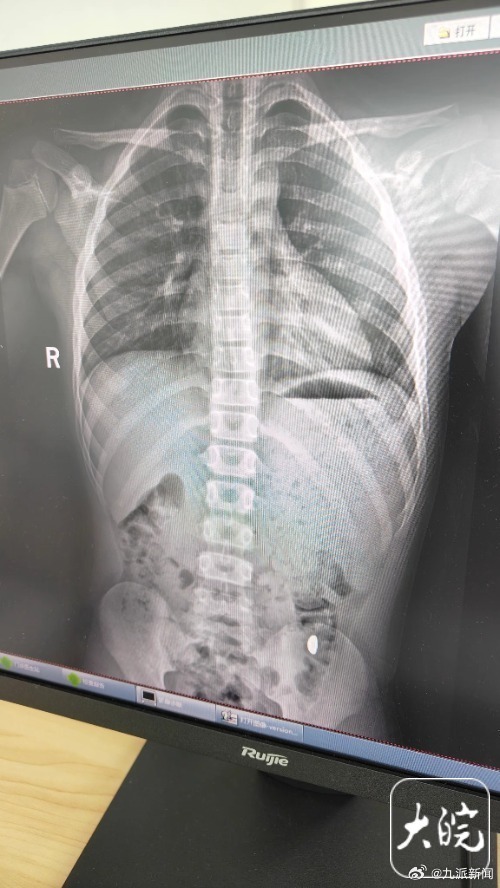

X光片显示金豆已运行到降结肠了,非在胃内。医生说胃内有异物是错误的。

#熊孩子误吞10克金豆6天后排出#【#孩子吞10克金豆妈妈称别在外上厕所#:这个屎有点贵,等了5天解2次大便未发现】“熊孩子说要锻炼舌头的力量,然后把我刚买的10克的金豆子吞下去了。”10月27日,江苏昆山纪女士向记者讲述了发生在她家孩子身上的奇葩事。纪女士介绍,10月17日她花费万元网购了一个10克重的金豆子,22日收到货后,她11岁的儿子把金豆子拿到屋里把玩,“当时我正在阳台洗衣服,他说‘妈妈你快过来,我要死了,我把金子给吞了’。”“我每天都提醒他不能在外面拉屎,这个屎有点贵。”纪女士说,她等了5天,对着大便扒拉了两次还是没有找到金子,于是10月26日,她就带儿子去了医院。昆山市第五人民医院门诊病历单显示,医生在现病史一栏写着,患儿5天前误吞约10克黄金,期间解2次大便未发现,目前无腹痛、呕吐等症状,诊断结果显示胃内有异物。“上午去的医院下午就拉出来了。”纪女士说,她把相关内容发布到社交平台,引起50多万人围观,她提醒,“大家一定要把家里的金子妥善存放,千万别让熊孩子看到。(大皖新闻)